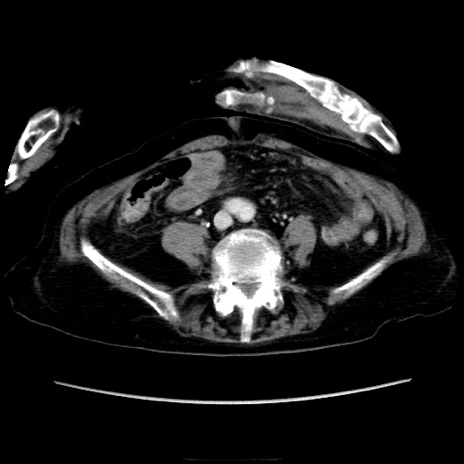

症例40(横断像)

横断像

冠状断像

矢状断像